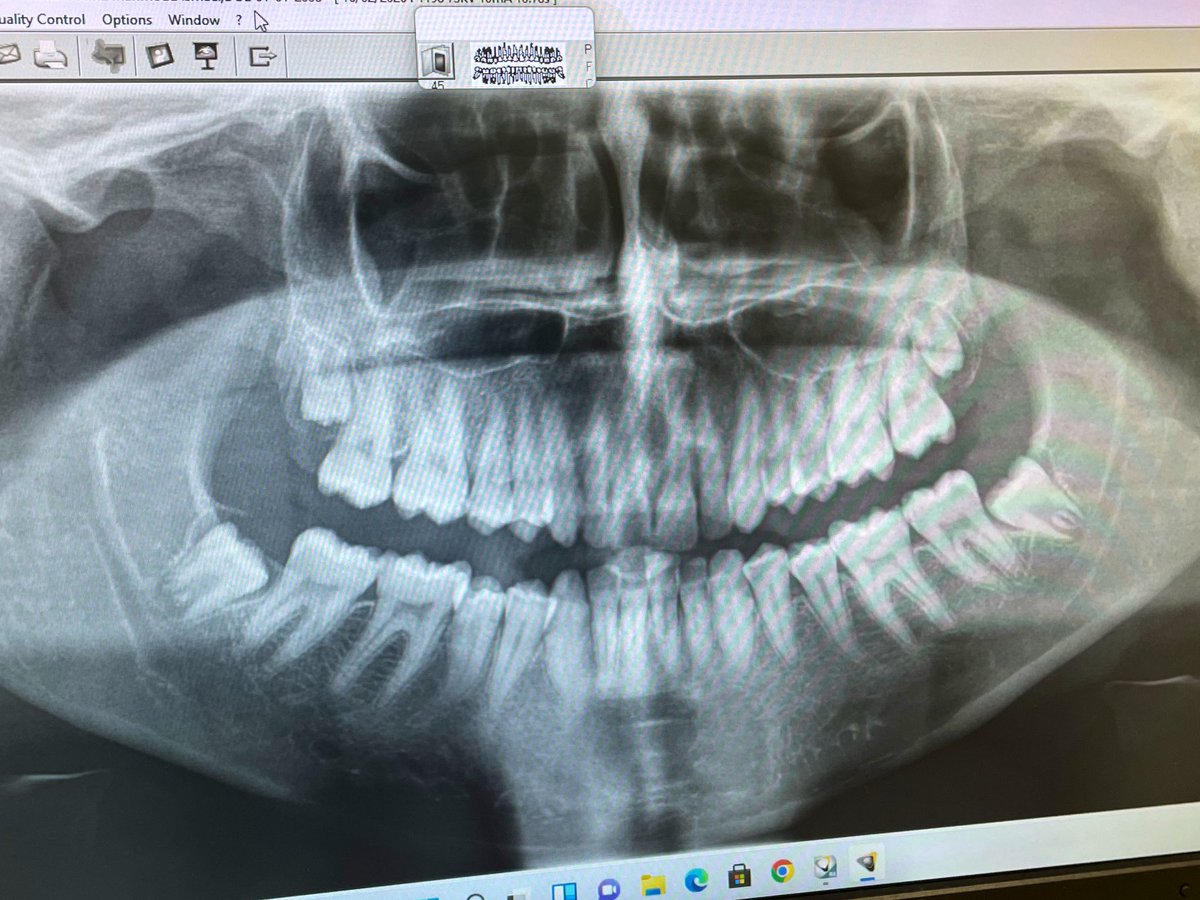

Intern Case Report – Endodontic Management of Tooth #22 with Periapical Abscess حضرت المريضة لاستكمال Endodontic treatment للسن رقم (22)، وكانت تعاني سريريًا من Periapical abscess مصحوب بأعراض ألم وتنميل. تم تحديد وتأكيد Working Length (WL) وبلغ 19.5 mm عند إجراء Canal negotiation تبيّن أن القناة Narrow canal، وعليه تم البدء بمرحلة Cleaning and Shaping باستخدام Hand files بشكل تدريجي حتى مقاس #35 بهدف إنشاء Glide Path آمن يسهّل إدخال الأدوات ويقلل من احتمالية حدوث Canal transportation أو Ledge formation أو Instrument separation. تم إجراء irrigation بصورة مستمرة خلال جميع مراحل التحضير لتعزيز Debridement وتقليل البكتيريا داخل القناة الجذرية. بعد تحقيق Preliminary enlargement مناسب، تم إدخال Rotary instrumentation ابتداءً من مقاس #20 لاستكمال Biomechanical preparation مع المحافظة على المسار التشريحي الأصلي للقناة. في نهاية الجلسة تم وضع Composite filling لضمان Coronal seal ومنع Reinfection .